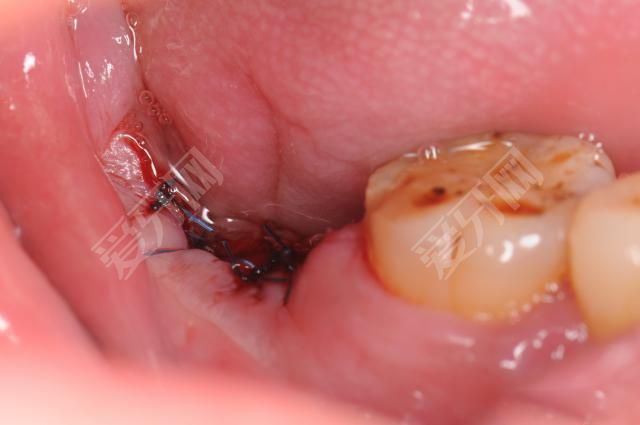

傷口裂開

這是由于種植牙時(shí)縫合過緊或過松造成的。特別是種植牙清潔不當(dāng),誘發(fā)感染時(shí),更容易導(dǎo)致局部傷口裂開。解決危害的方法是及時(shí)清創(chuàng),重新縫合,避免種植體暴露。

出血

種植牙是微創(chuàng)手術(shù),種植牙后應(yīng)該沒有出血。為何種植牙會(huì)導(dǎo)致血光之災(zāi)?此時(shí)由于種植牙技術(shù)不到位,由于種植牙對(duì)牙周組織還是有一定的損傷,如果牙醫(yī)在粘骨膜剝離時(shí)損傷較大或粘膜下剝離較廣,特別是術(shù)后壓迫不良,都容易發(fā)生粘膜下或皮下出血。

另外一種種植牙出血的情況,是在一期手術(shù)中種植牙釘時(shí),種植體穿出下頜下緣,還可能發(fā)生下頜淤血。局部淤血一般可以在幾天后吸收,術(shù)后早期冷敷,晚期熱敷。但是,如果接受種植牙的患者因全身因素而有出血傾向,應(yīng)對(duì)癥治療。